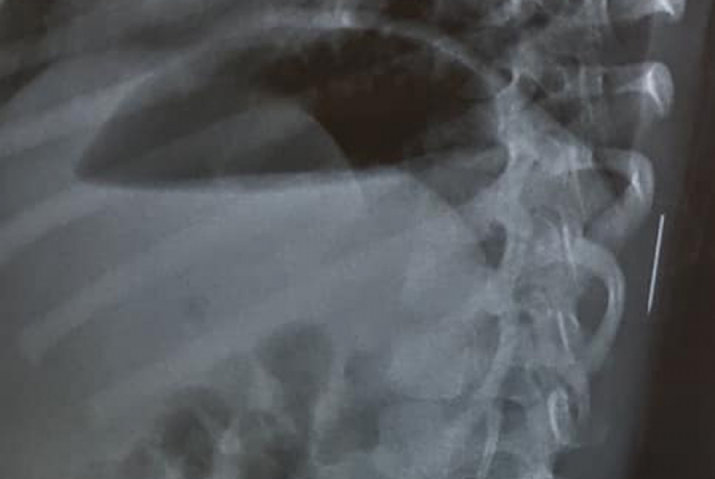

Bé gái 40 tháng tuổi uống nhầm dầu hỏa, bị viêm phổi nặng

VOV.VN -Bệnh nhi vào viện trong tình trạng kích thích, tăng tiết đờm dãi, tim đập nhanh, phổi thông khí kém và được chẩn đoán viêm phổi nặng do ngộ độc dầu